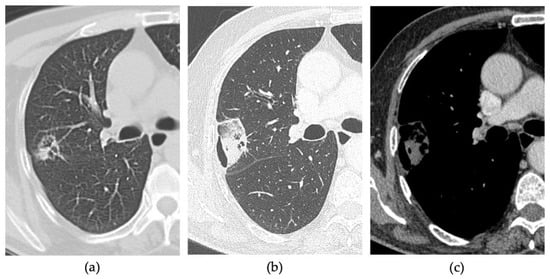

- Vespro, V.; Bonanno, M.C.; Andrisani, M.C.; Ierardi, A.M.; Phillips, A.; Tosi, D.; Mendogni, P.; Franzi, S.; Carrafiello, G. CT after Lung Microwave Ablation: Normal Findings and Evolution Patterns of Treated Lesions. Tomography 2022, 8, 617–626. [Google Scholar] [CrossRef]